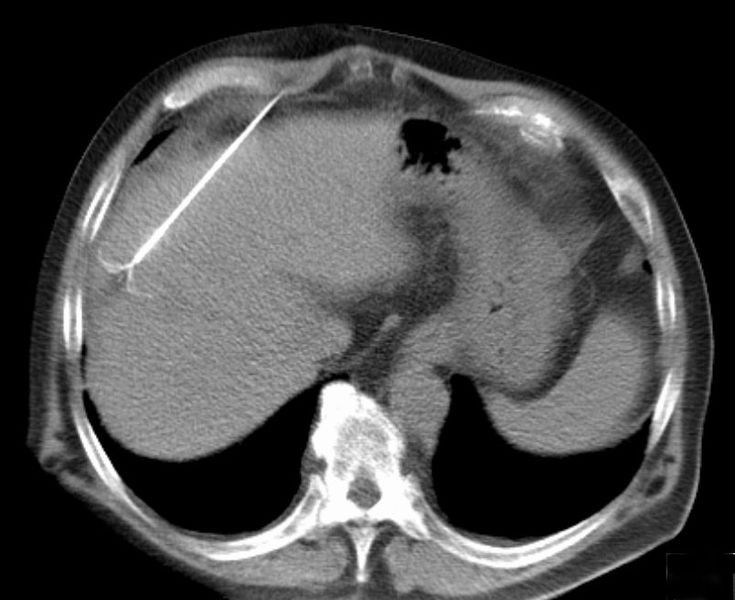

| CT scan showing radiofrequency ablation of a liver lesion |

RFA is used to treat numerous tumors including those in the liver, bone, kidney, and lung. A key advantage is it selectively destroys cancer cells while leaving healthy cells unaffected. The size and location of tumors are a factor in whether RFA can be used.